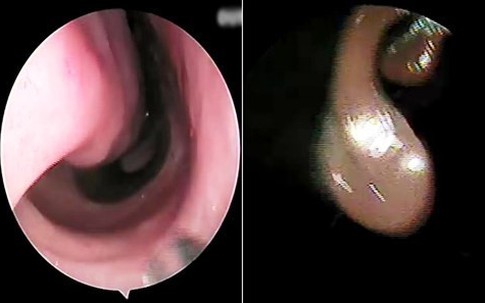

Gắp chiếc đinh ghim sắt nhọn hoắt trong phế quản bé gái 12 tuổi

GiadinhNet - Trong lúc chơi đùa với em gái, bé Thương nhặt được chiếc đinh ghim bằng sắt có đế nhựa loại thường dùng để ghim giấy nên đã cầm nghịch chơi. Trong lúc chơi bé cho đinh ghim vào miệng và sơ ý nuốt phải.